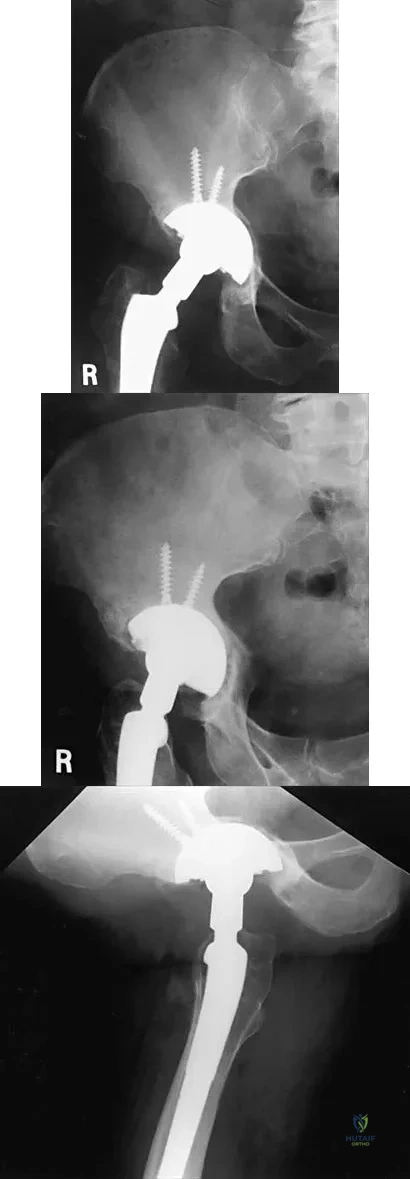

Figures 21a through 21c show the radiographs of a 70-year-old woman who has persistent pain with activity after undergoing hip revision 6 months ago. Treatment should now consist of

Explanation